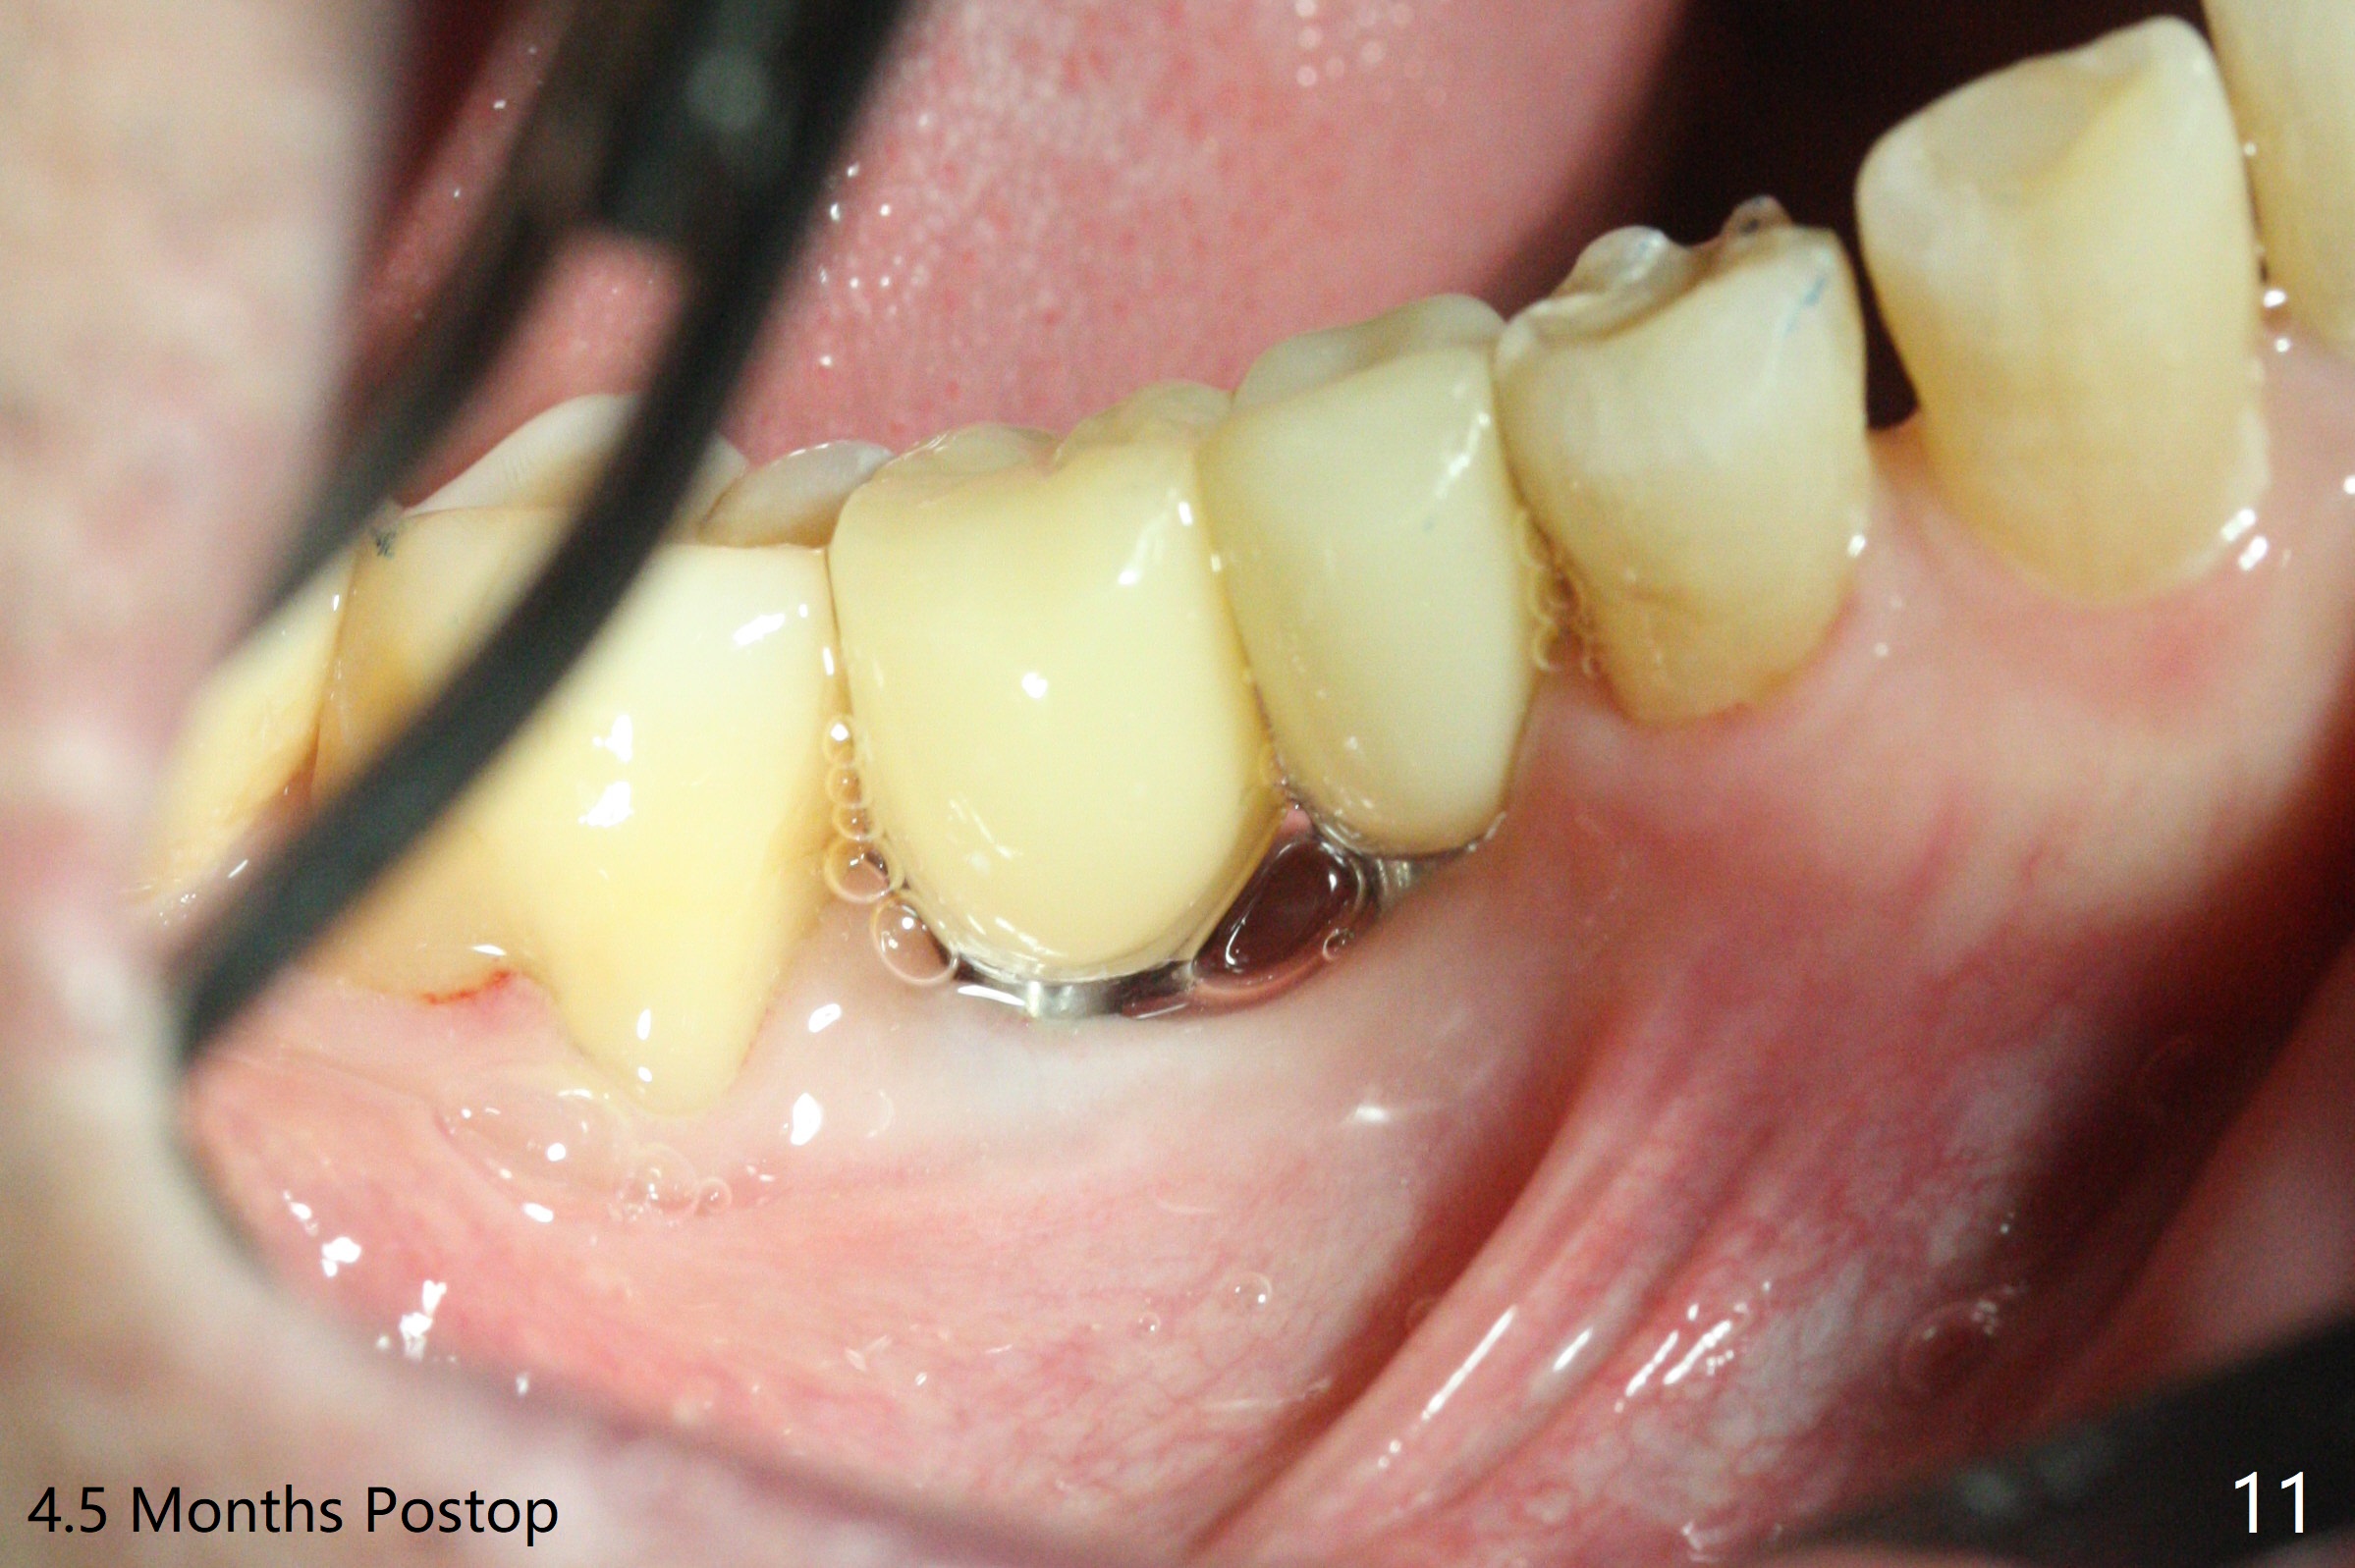

After initial osteotomy using 2.2 mm drill for 10 and 11.5 mm at #29 and 30, respectively, the guide is removed for re-insertion of drills and PA (Fig.1). The osteotomy at #29 is found lingually and in the nonkeratinized gingiva with mild laceration (wish incision to be made before osteotomy); the osteotomy is established a little lingual at #29 (Fig.2) and more or less in the middle of the narrow ridge and #30 (Fig.3). Lindamann bur is used to move #29 osteotomy buccally. A 1.5 mm drill is used to increase the depth free hand before placement of 2.5x10(4) mm 1-piece implants (Fig.4). After adjustment of the implant depth (Fig.5), CT is retaken, which shows proper implant placement (Fig.6,7). Probably due to good oral hygiene, the gingiva around the implants appears to be keratinized 4 months postop (Fig.8). After abutment preparation for margin and parallelism, impression is taken (Fig.9). When the permanent crowns are temporarily cemented, the large gingival embrasure is noted (Fig.10,11). The latter could be reduced by modifying the provisional in the healing stage. In fact the crown at #29 dislodges 2 days post cementation because lingual (Fig.12) and distal (Fig.13) placement. A surgical stent should have been fabricated from RPD for free hand placement!